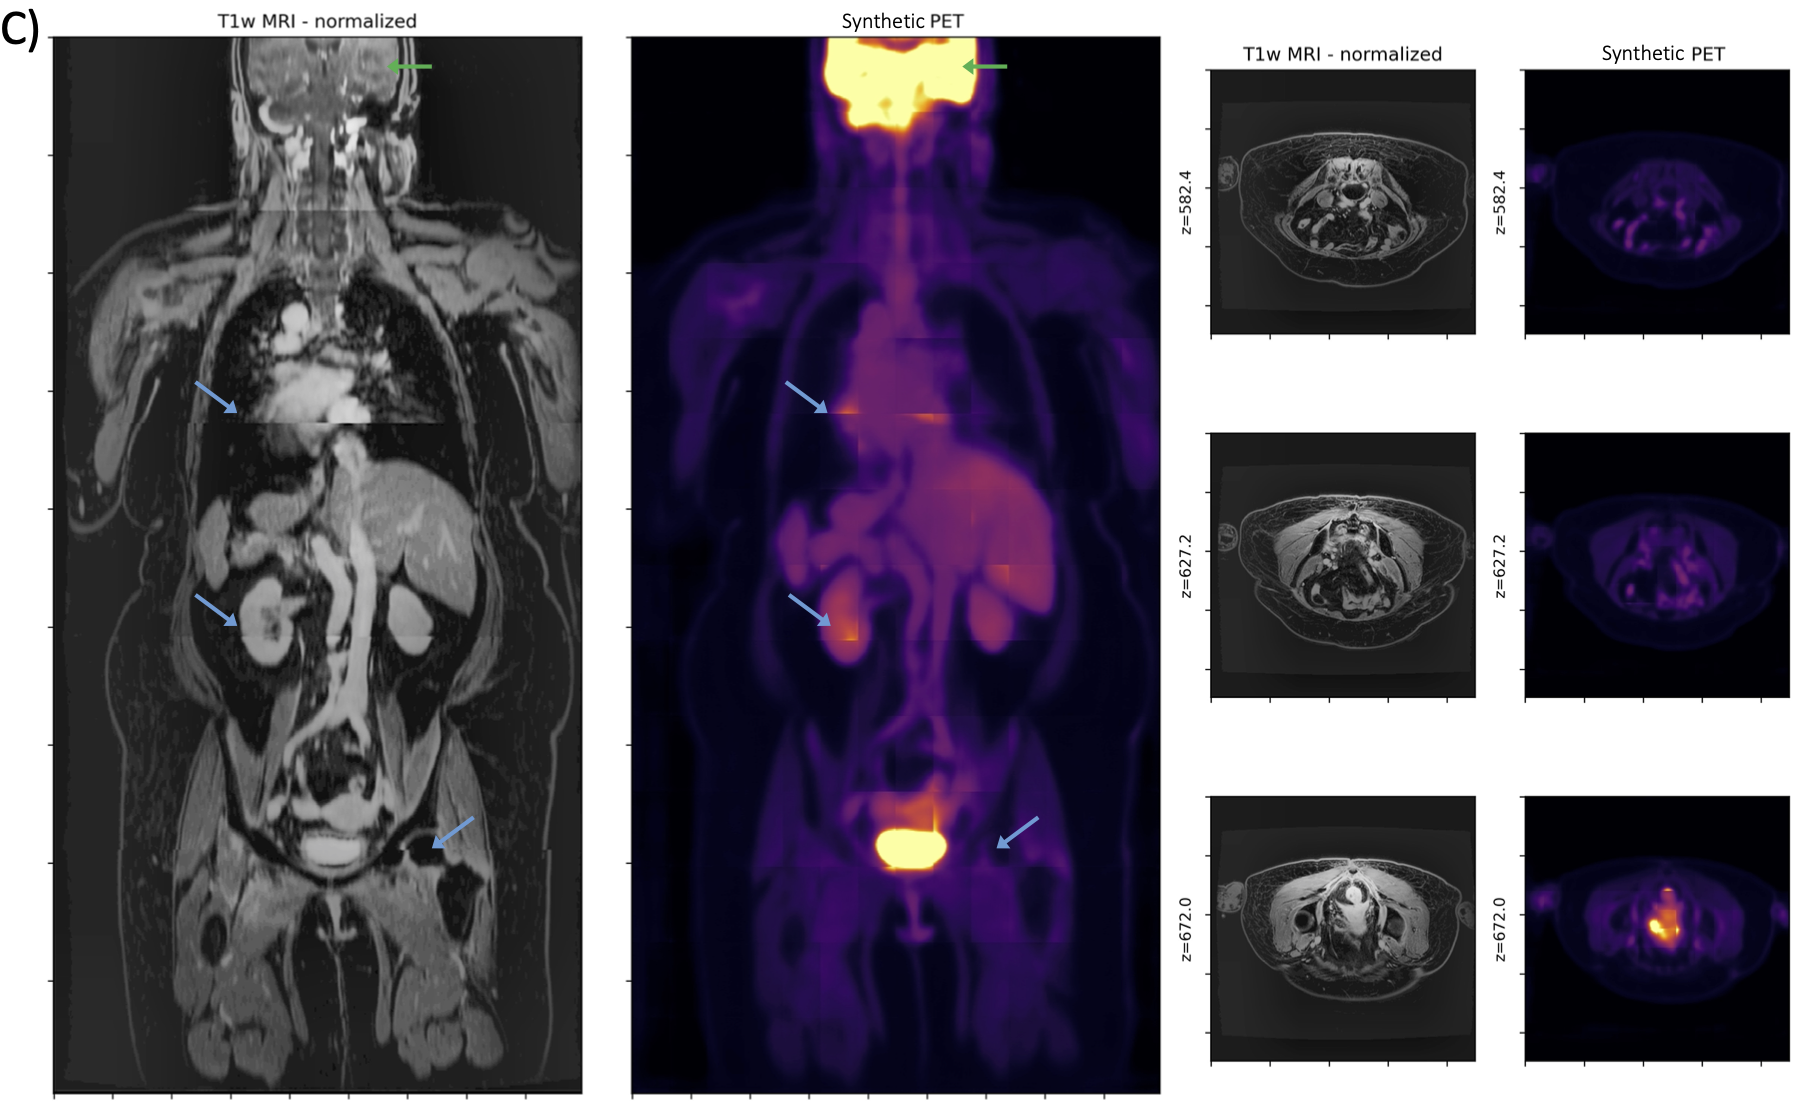

We find that prediction of synthetic FDG-PET, domain-translated from T1-weighted post-contrast MRI, works well despite the lack of salient tracer-specific or functional information in MRI (Fig. 3). Numerical results comparing the effect of different training objectives on test-set performance is shown in Table 1. Qualitative analysis reveals that physiologic uptake is predicted accurately and reconstructed seamlessly throughout the body without obvious spatial artifacts, except in regions where we expect variable uptake (e.g. heart, bladder). In the myocardium, for example, FDG-PET uptake depends on patient metabolism, which can vary across exams for even a single patient. Similarly, in the bladder PET uptake is often dependent on a patient’s water consumption and timing of voiding [34].